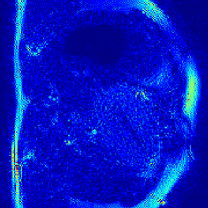

IV-C Compressive Sensing Dynamic MRI Reconstruction

The proposed method is tested on the retrospective cardiac cine dataset OCMR[53]. The detailed information of the dataset is listed in the supplementary file. The acquired data are transformed into the -space domain using the multi-channel NUFFT implementation with golden-angle radial trajectories based on Fibonacci number sequencing. Coil sensitivity maps are derived through the ESPRIT algorithm[54] to enable parallel imaging reconstruction. Different acceleration factors (AFs) are simulated for evaluation, including 21, 13, 8, 5, 3, 2, 1 spokes per frame (AF=9.7, 15.7, 25.5, 40.8, 67.9, 101.9, 203.7).

We select four representative baselines, including the NUFFT that provides direct zero-filled reconstructions without additional processing; the GRASP [39] that incorporates temporal frame grouping, time-averaged coil sensitivity estimation, and TV regularization; the FMLP [41] that employs INR and Fourier feature encoding for reconstruction; and the InstantNGP [24] that employs the multi-resolution hash grid encoding for dynamic MRI reconstruction.

IV-C2 Results

The quantitative results for compressive dynamic MRI reconstruction are shown in Table V. The proposed GridTD method outperforms competing methods across all evaluated settings in PSNR and SSIM metrics. Compared to other unsupervised deep learning methods FMLP and InstantNGP, our GridTD is over 50% faster due to the compact model structure. In Fig. 6, we present some visualizations of the reconstructed MRIs and the corresponding error maps, which demonstrate that GridTD better preserves structural edges and robustly recovers fine details, showing the superiority of our method for dynamic MRI reconstruction. All these results on video SCI, spectral SCI, and dynamic MRI reconstruction validate the strong performance of GridTD, positioning it as a versatile and state-of-the-art approach for compressive imaging reconstruction.